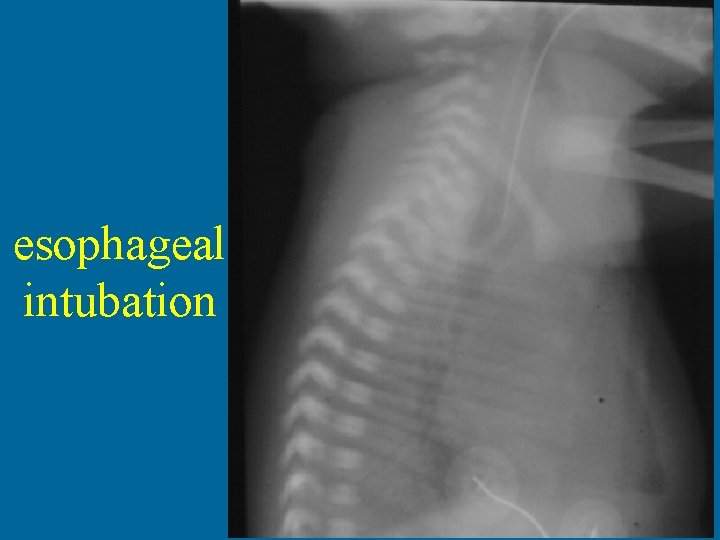

Where is the tube?

esophageal intubation